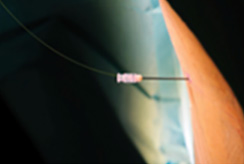

In the procedure of percutaneous laser disc decompression, laser energy is transmitted through a thin optical fiber into the disc.

The PLDD treatment is performed on an outpatient basis using only local anesthesia. During the procedure, a thin needle is inserted into the herniated disc under x-ray or CT guidance. An optical fiber is inserted through the needle and laser energy is sent through the fiber, vaporizing a tiny portion of the disc nucleus. This creates a partial vacuum which draws the herniation away from the nerve root, thereby relieving the pain. The effect usually is immediate.

- Sterilized optical fiber 400um/600um for medical use

- Cervical: 18G 10cm puncture needle

- Lumbar region:18G 15cm puncture needle